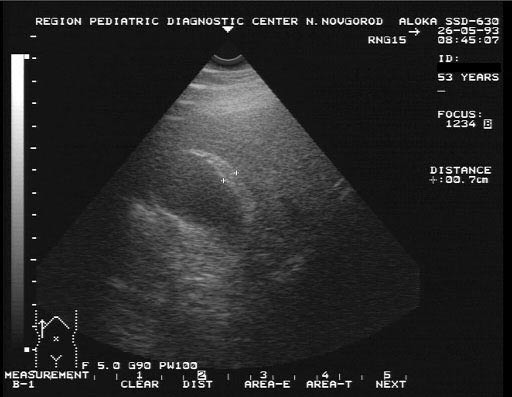

Информативность УЗИ-диагностики составляет 95-98%. Затруднения при этом исследовании могут наблюдаться при небольших размерах камня. В норме длина желчного пузыря составляет 7-10 диаметр около 3 объем колеблется от 30 до 70 мл, толщина передней стенки желчного пузыря 2-3 Конкремент определяется как округлое, эхогенное образование, с типичной акустической дорожкой при размерах более 0,5 Холестериновые камни легче желчи, поэтому они «плавают» в желчном пузыре.

Распространено проведение диагностического УЗИ после желчегонного завтрака.